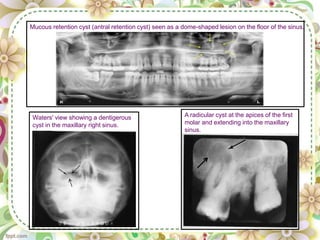

Odontogenic Cystic Lesion

• Odontogenic cysts

are the most common

group of extrinsic

lesions that encroach

on the maxillary

sinuses.

• The cyst enlarges ,the

sinus decrease in size

• The result is radio-

opaque line between

the cyst and the air

space of the sinus.

A radicular cyst at the apices of the first

molar and extending into the maxillary

sinus.

Waters' view showing a dentigerous

cyst in the maxillary right sinus.

Mucous retention cyst (antral retention cyst) seen as a dome-shaped lesion on the floor of the sinus.